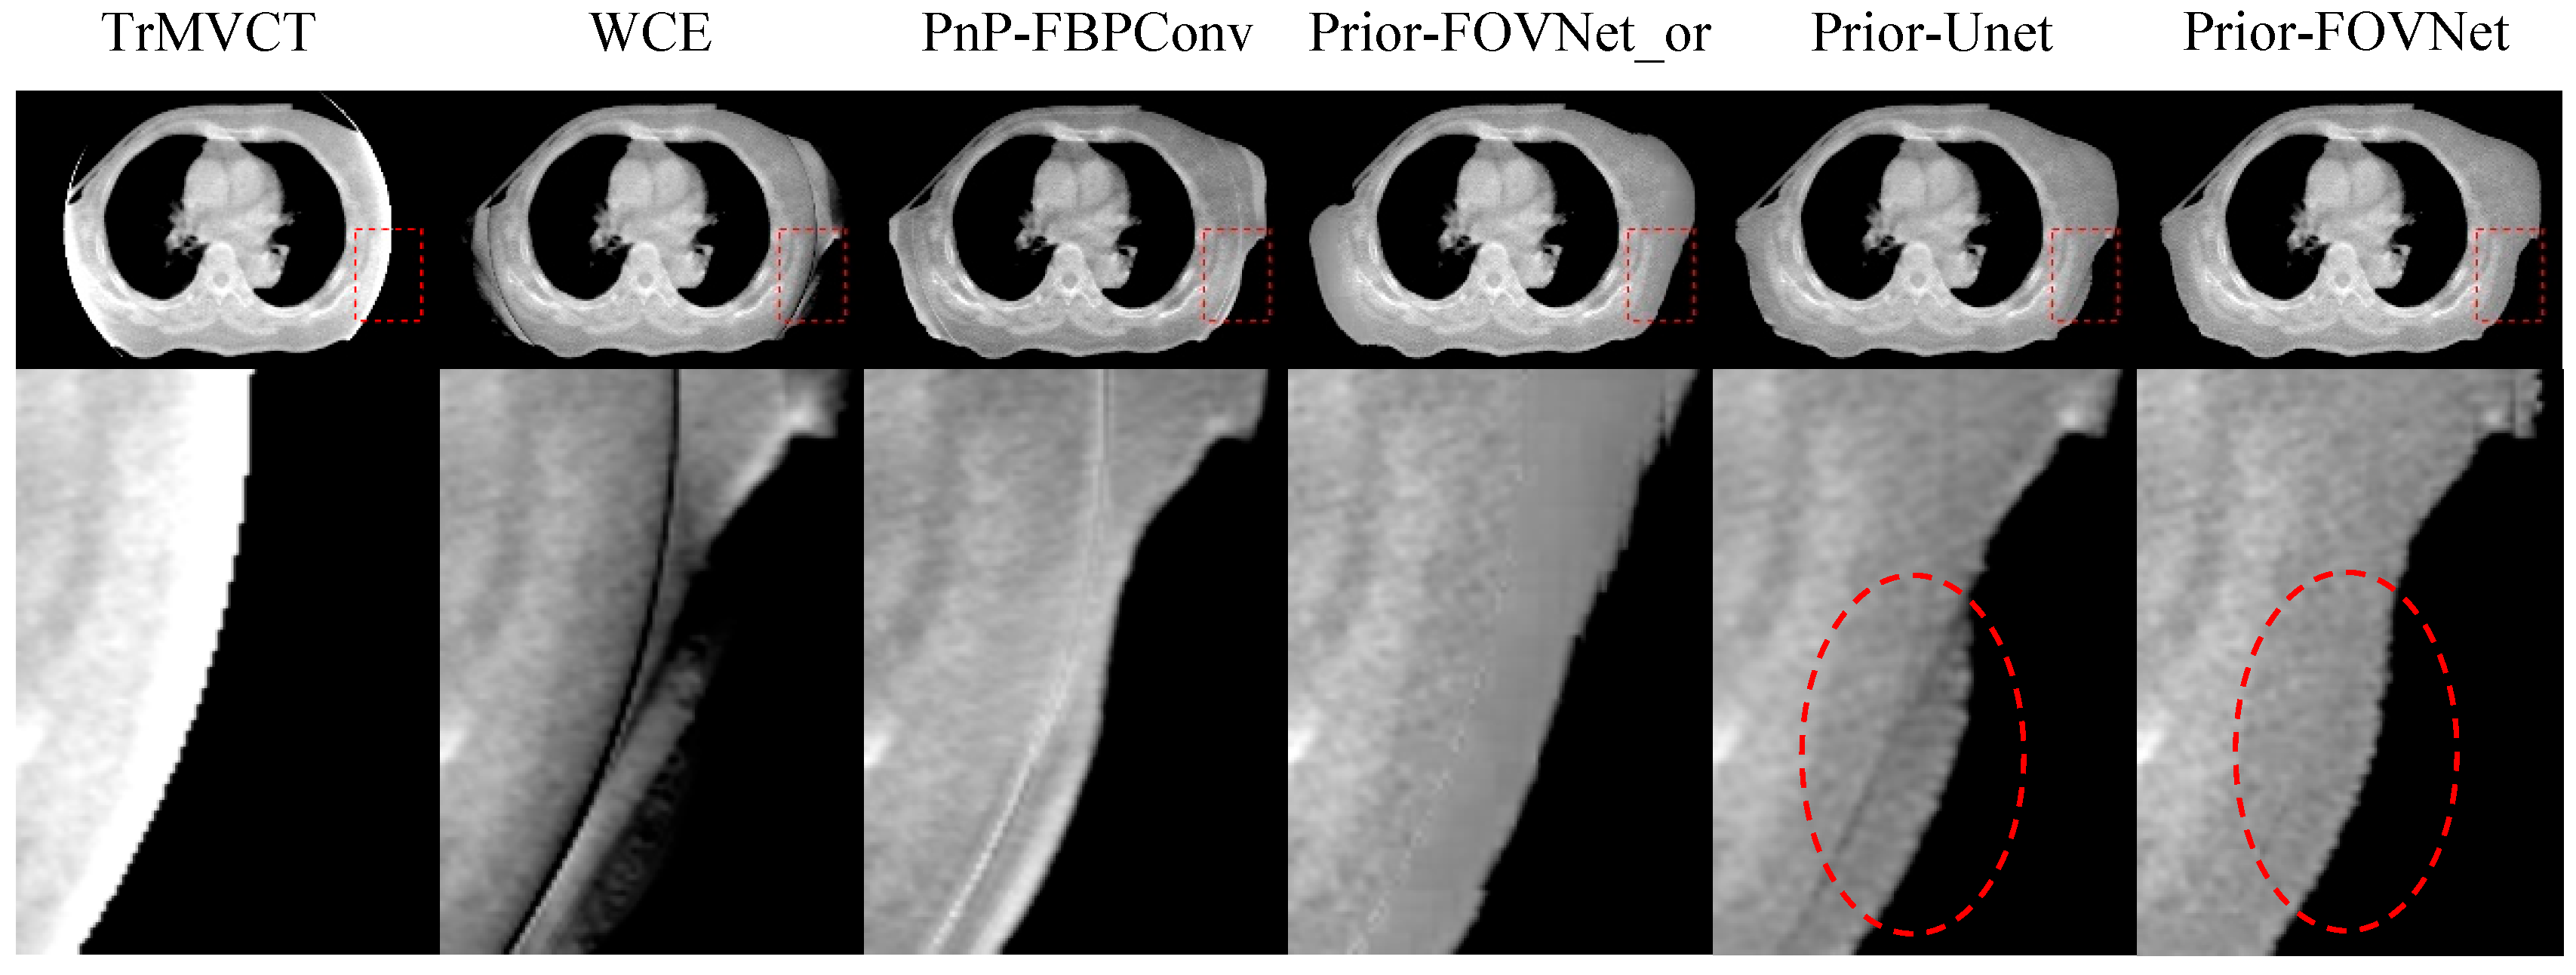

| Symmetrical Extrapolation | WCE | PnP-FBPConv | Prior-FOVNet-or | Prior-Unet | Prior-FOVNet | |

|---|---|---|---|---|---|---|

| MAE | 189.3 ± 52.5 | 93.5 ± 33.5 | 38.0 ± 3.6 | 60.8 ± 28.4 | 40.3 ± 10.5 | 23.8 ± 5.6 |

| RMSE | 277.1 ± 72.9 | 209.2 ± 64.3 | 61.6 ± 11.3 | 182.4 ± 76.2 | 100.6 ± 42.6 | 50.8 ± 18.4 |

| SSIM | 85.6 ± 3.4 | 89.0 ± 4.2 | 95.8 ± 1.0 | 94.6 ± 1.6 | 95.4 ± 1.1 | 97.8 ± 0.6 |